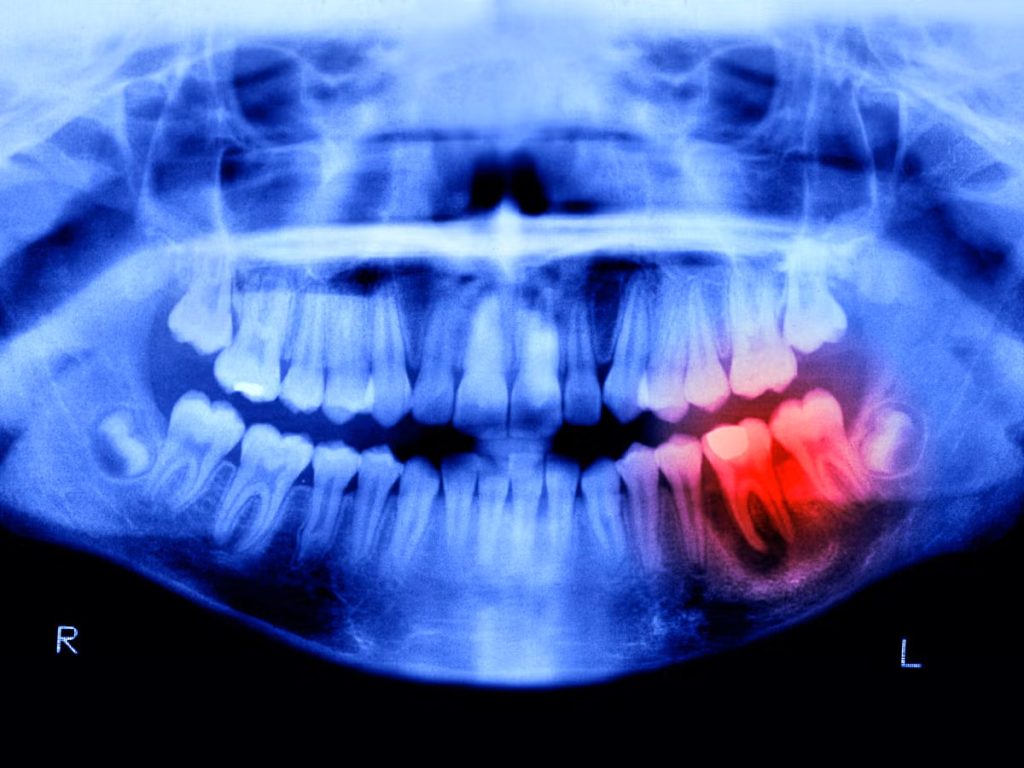

Επανάσταση στην οδοντιατρική: Νοτιοκορεάτες κατάφεραν να φύονται νέα δόντια σε ενήλικες όπως στα μωρά! Νοτιοκορεάτες επιστήμονες αποκάλυψαν ότι πραγματοποίησαν μια πρωτοποριακή οδοντιατρική καινοτομία — ένα μικροσκοπικό βιοδραστικό έμπλαστρο ικανό να αναγεννά πραγματικά δόντια με φυσικό τρόπο, ενδεχομένως τερματίζοντας την εποχή των τεχνητών οδοντοστοιχιών.

Αντί να βασίζεται σε τεχνητά εμφυτεύματα, αυτό το έμπλαστρο ενεργοποιεί τα ίδια τα βλαστοκύτταρα του σώματος μέσα στη γνάθο, ξεκινώντας την αναγέννηση του σμάλτου, της οδοντίνης, ακόμη και ολόκληρων δομών των δοντιών!

Τοποθετημένο ακριβώς πάνω από το σημείο ενός δοντιού που λείπει, παρέχει ακριβή βιοχημικά σήματα που αφυπνίζουν αδρανείς αναγεννητικές οδούς, επιτρέποντας σε ένα νέο δόντι να αναπτυχθεί μέσα από τα ούλα — με φυσική λειτουργία και αίσθηση.